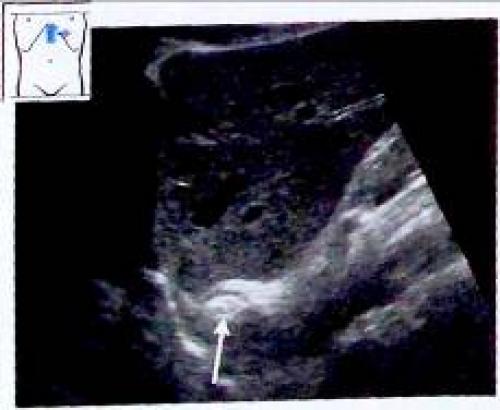

Визуализация тела желудка на продольном сечении

У неподготовленного к обследованию пациента тело желудка визуализируется только как постоянно изменяющееся поле позади левой доли печени. При имеющемся исходном изображении гастроэзофагеального перехода найти эту область достаточно просто.

Рис. 6. Визуализация тела желудка на продольном сечении:

продольное сечение через печень и гастроэзофагеальный переход (^);

Рис. 7. Визуализация тела желудка на продольном сечении:

датчик смещен влево. Срез желудка расширился (v);

Рис. 8. Визуализация тела желудка на продольном сечении: латеральное продольное сечение. Видна полость желудка, заполненная твердыми частицами и газом (v

В случае если ультразвуковой сигнал попадает на стенку желудка по касательной, проходя при этом через многочисленные складки слизистой оболочки, может сформироваться ошибочная картина утолщения стенки желудка (см. рис. 5). С другой стороны, массивный отек стенки желудка может быть не диагностирован даже при наличии у пациента клинических проявлений (анорексия, снижение массы тела, вздутие живота, отвращение к жареной пище), в случае если не удается осуществить визуализацию всех отделов желудка. Для оценки тела желудка исследование выполняется в левой косой подреберной плоскости, для оценки кардиального отдела и входа в желудок - в высокой продольной околосрединной плоскости выше аортального отверстия диафрагмы.

Рис. 9. Многочисленные складки слизистой оболочки могут имитировать утолщение стенки желудка, в случае если они располагаются по касательной к ультразвуковому сигналу.